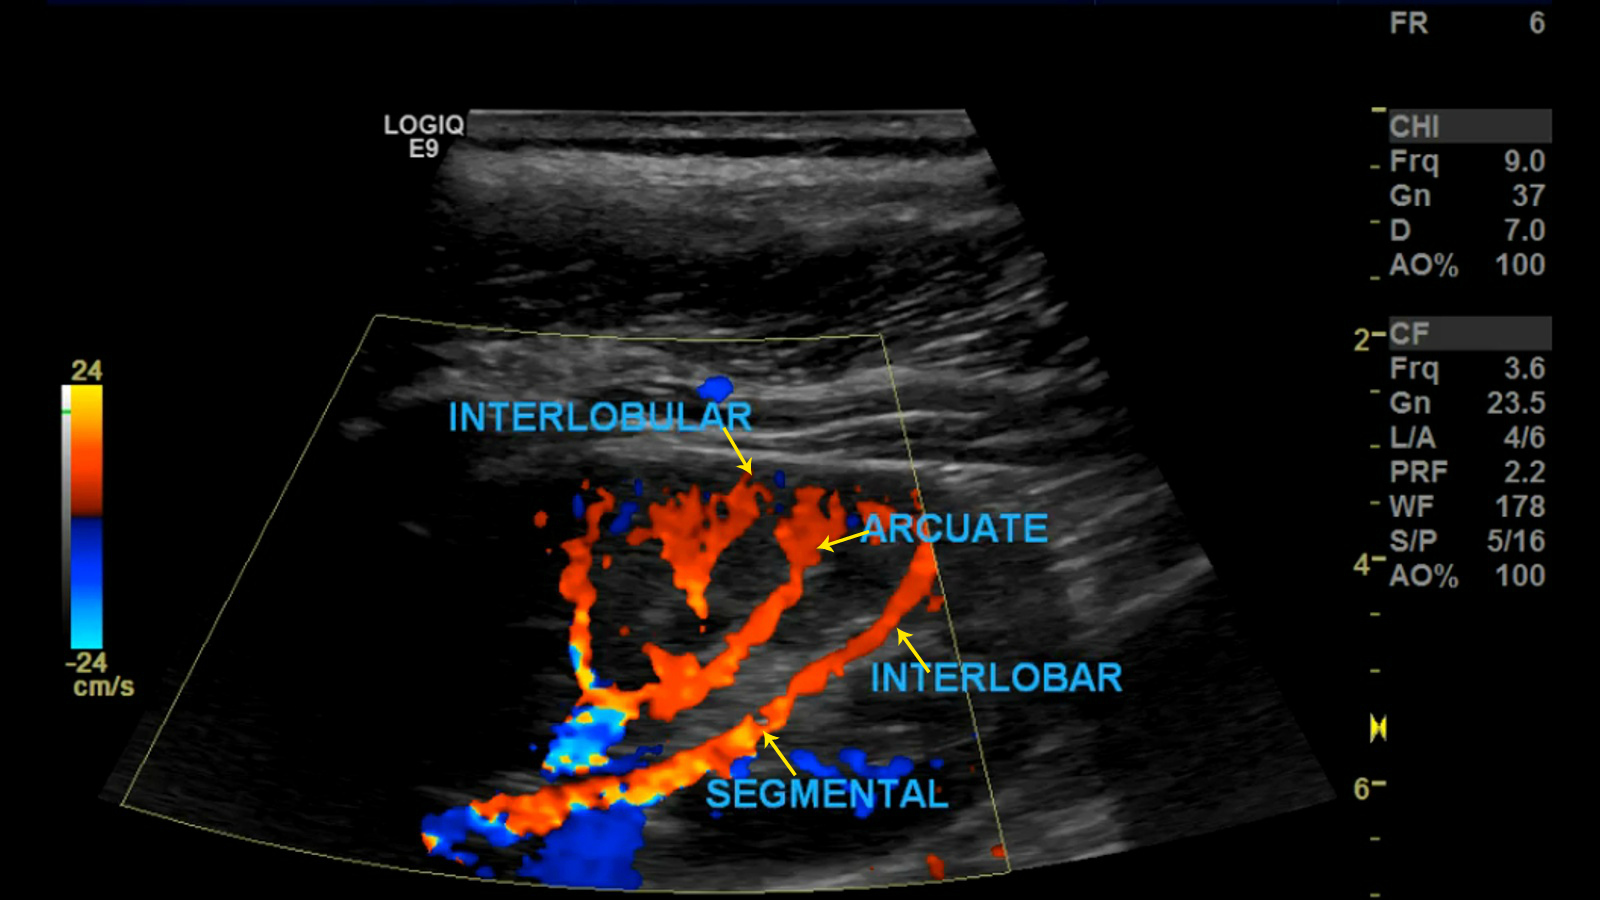

Renal Artery Doppler